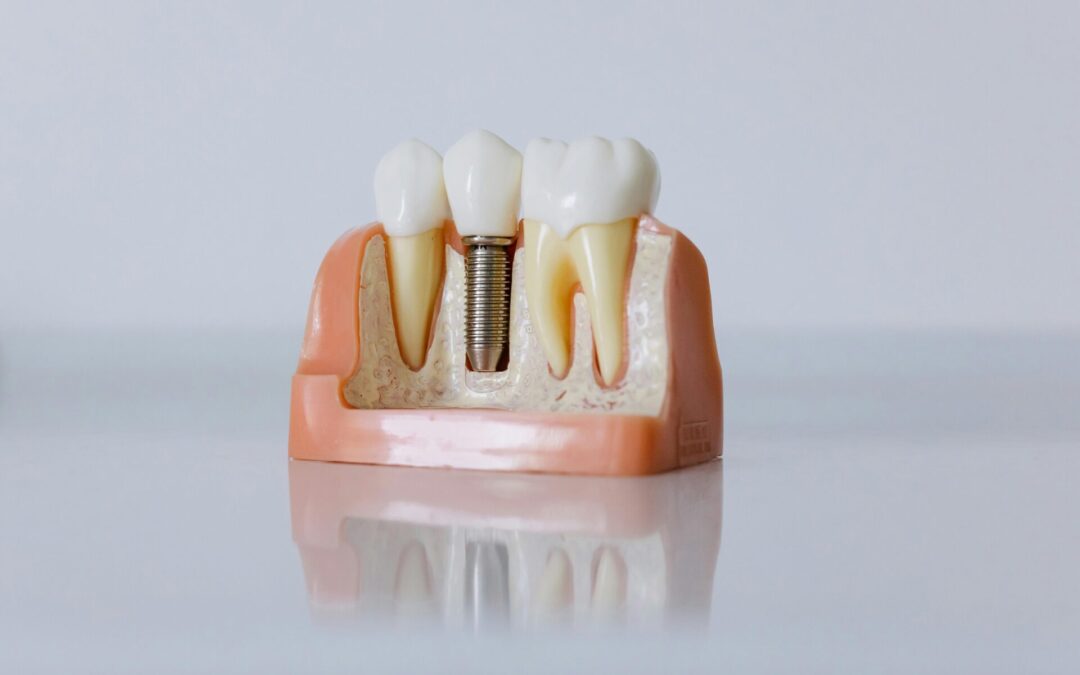

• Implant Dentistry & Full Mouth Reconstruction

• Zirconia Ceramic Implants